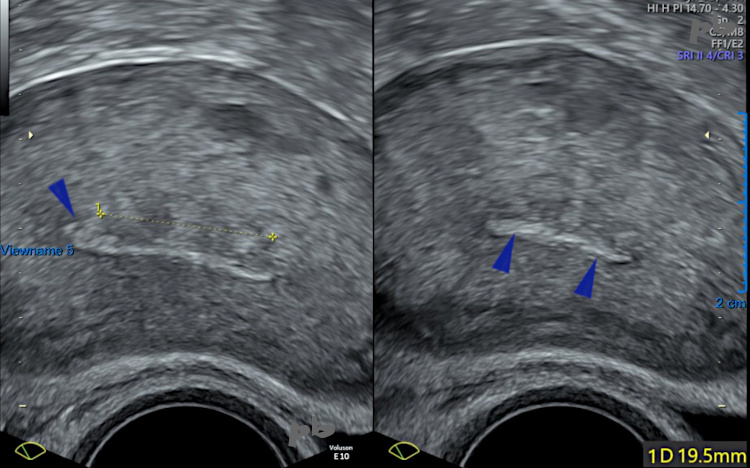

3 – Résidu trophoblastique

Coupes transversales de l’utérus.

A droite, l’endomètre parait fin et régulier, sans trophoblaste résiduel.

A gauche, on voit en fait l’endomètre (►) moulant une image isoéchogène au myomètre (entre les croix) : résidu trophoblastique.

Evacuation spontanée.